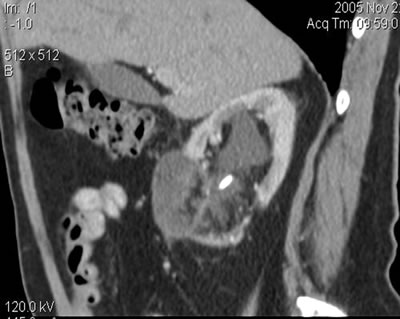

Мониторинг

(7 месяцев)

Спиральная компьютерная томография

(СКТ)

в нижнем сегменте - образование

размером 39х36х28 мм, при болюсном усилении - накапление

контрастного вещества (max 20-23 HU)

(10 месяцев) 22 ноября 2005

размером 37х35х27 мм, при болюсном усилении накапление

контрастного вещества (max 21-23 HU)